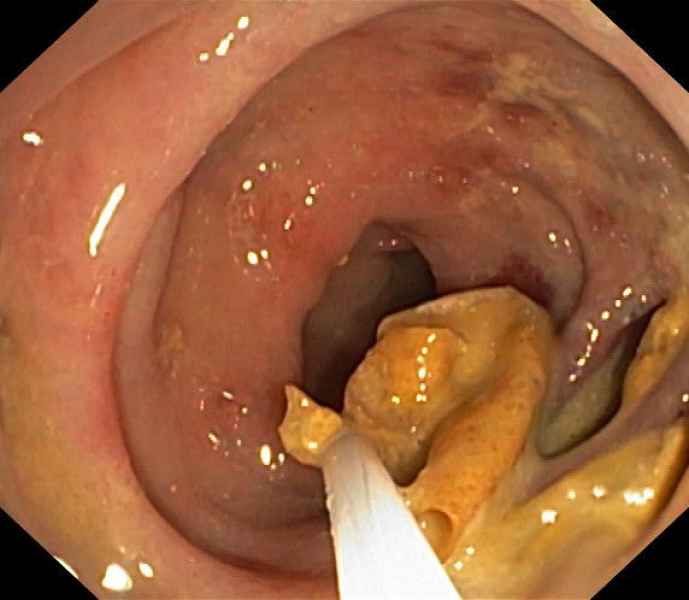

An uncommon diagnosis done by colonoscopy

Colocolic intussusception